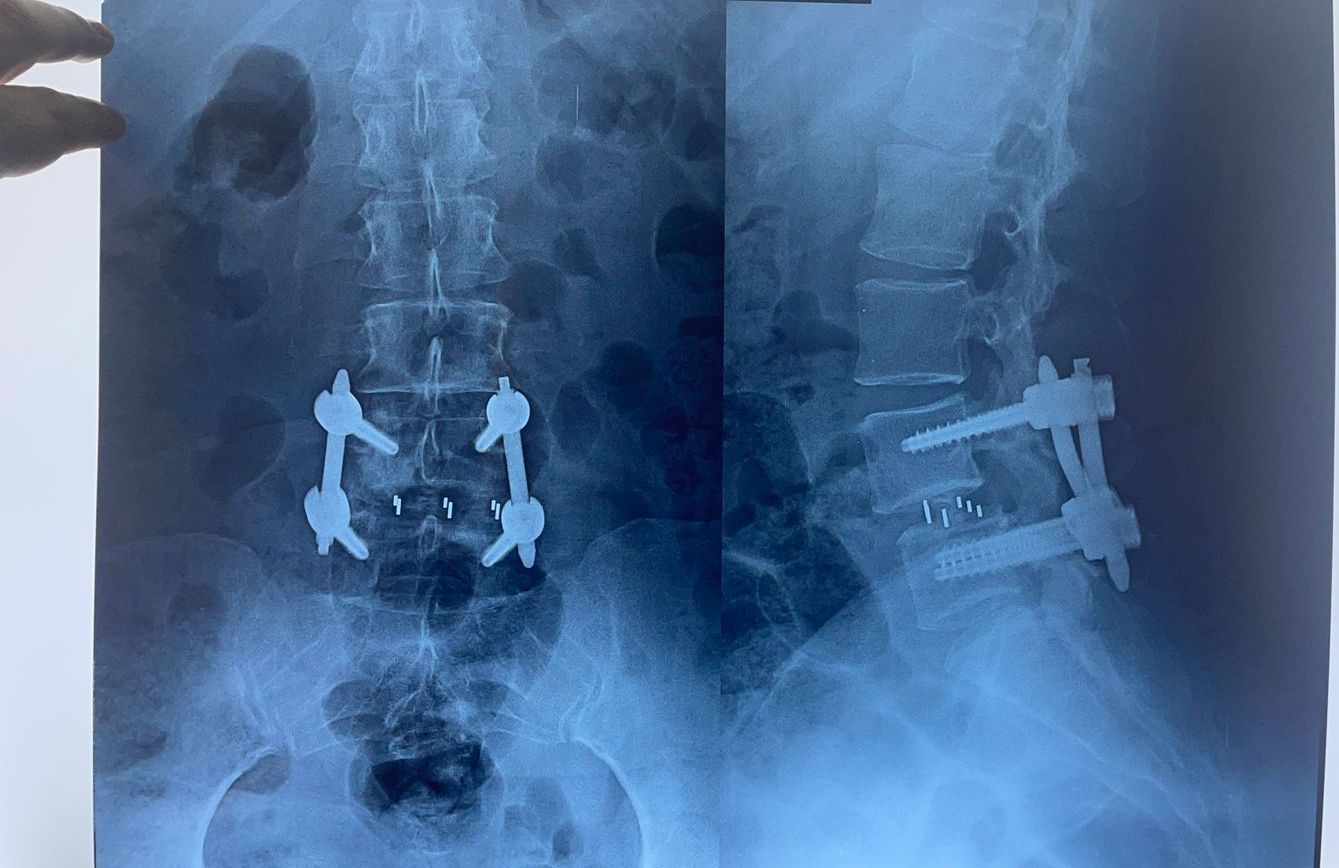

Espondilolistesis

La espondilolistesis es una condición en la cual una vértebra se desliza hacia adelante sobre la vértebra adyacente. La endoscopia biportal puede utilizarse para realizar una fusión espinal mínimamente invasiva, estabilizando las vértebras afectadas y aliviando los síntomas del paciente.